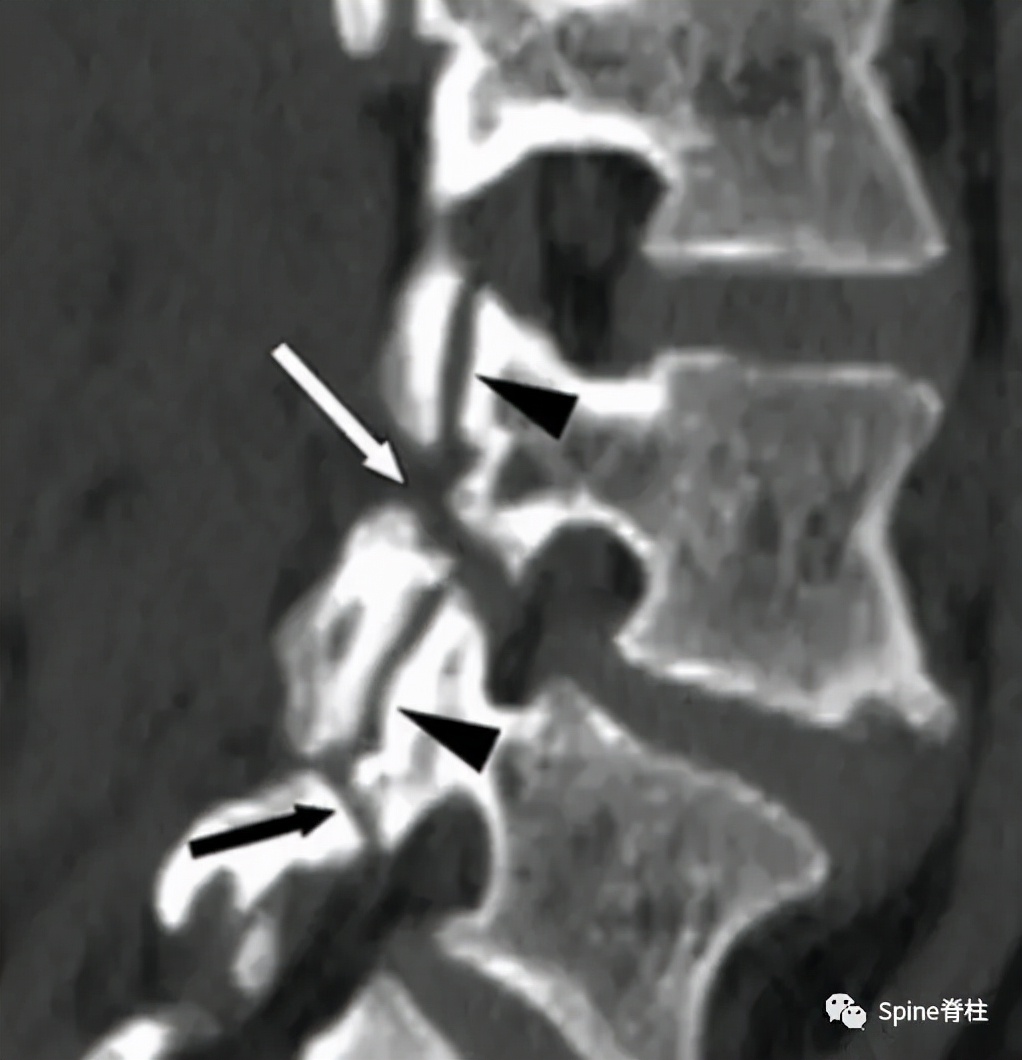

- 椎弓根裂 (pediculolysis)是指椎弓根的应力性骨折,常发生在单侧峡部裂的对侧椎弓上。表现为矢壮位MRI的椎弓根呈T1低信号和T2高信号(水肿信号),伴或不伴骨折线。

图:15岁腰痛男孩,左侧腰5椎弓根裂

A:T1左侧腰5椎弓根低信号(箭头);B:T2左侧腰5椎弓根高信号(箭头);C:T2轴位左侧腰5椎弓根骨折线明显,伴高信号区(箭头)。

- 椎板裂病例

图:17岁腰痛男孩,L5双侧峡部裂和右侧椎板裂

C:右侧椎板增厚,不连续

图:起始CT提示L5左侧峡部裂(双箭头),起始CT检查后2个月复查可见出现右侧椎弓根裂(单箭头),4个月复查可见椎弓根裂愈合(单箭头)。

图:6个月复查可见右侧椎弓根裂已愈合(单箭头),但出现右侧峡部裂(双箭头)